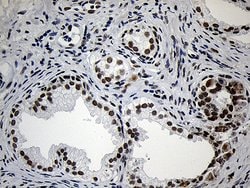

ZNF670 Monoclonal Antibody for Western Blot, IHC (P)

| Immunohistochemistry (Paraffin), Western Blot | |